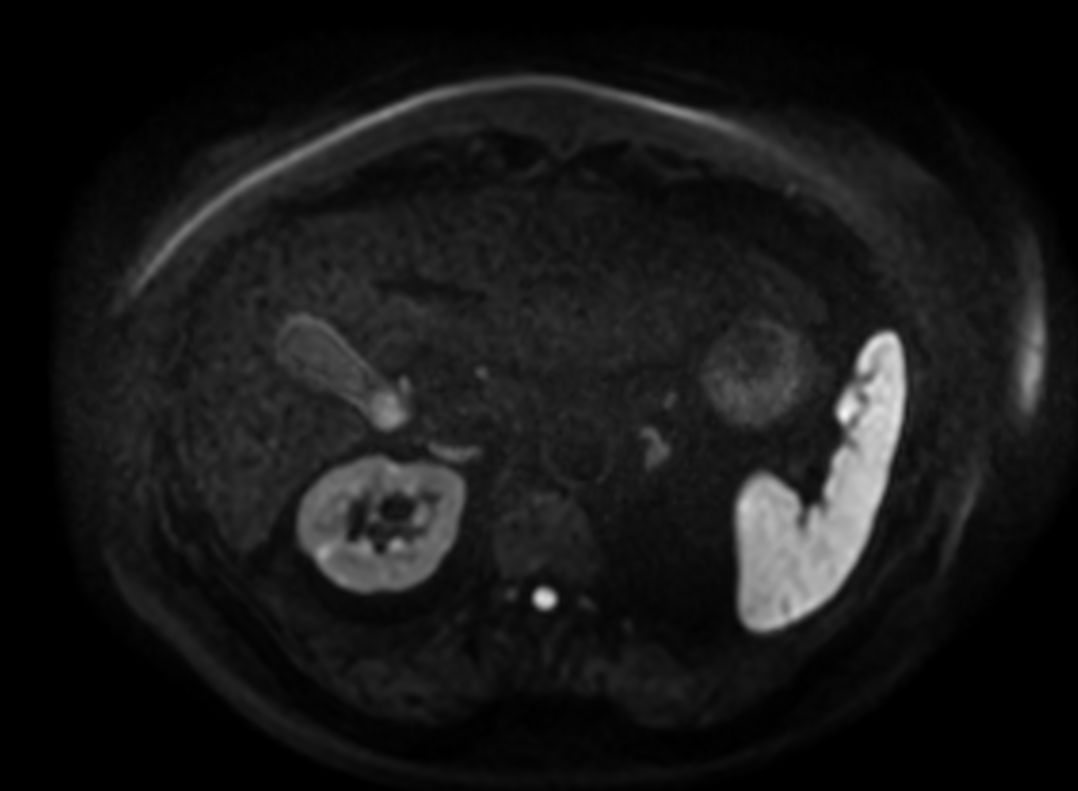

mDIXON XD Quant (Water only)

-

mDIXON XD Quant (Fat only)

mDIXON XD Quant (Fat Fraction Map)

mDIXON XD Quant (T2* Map)